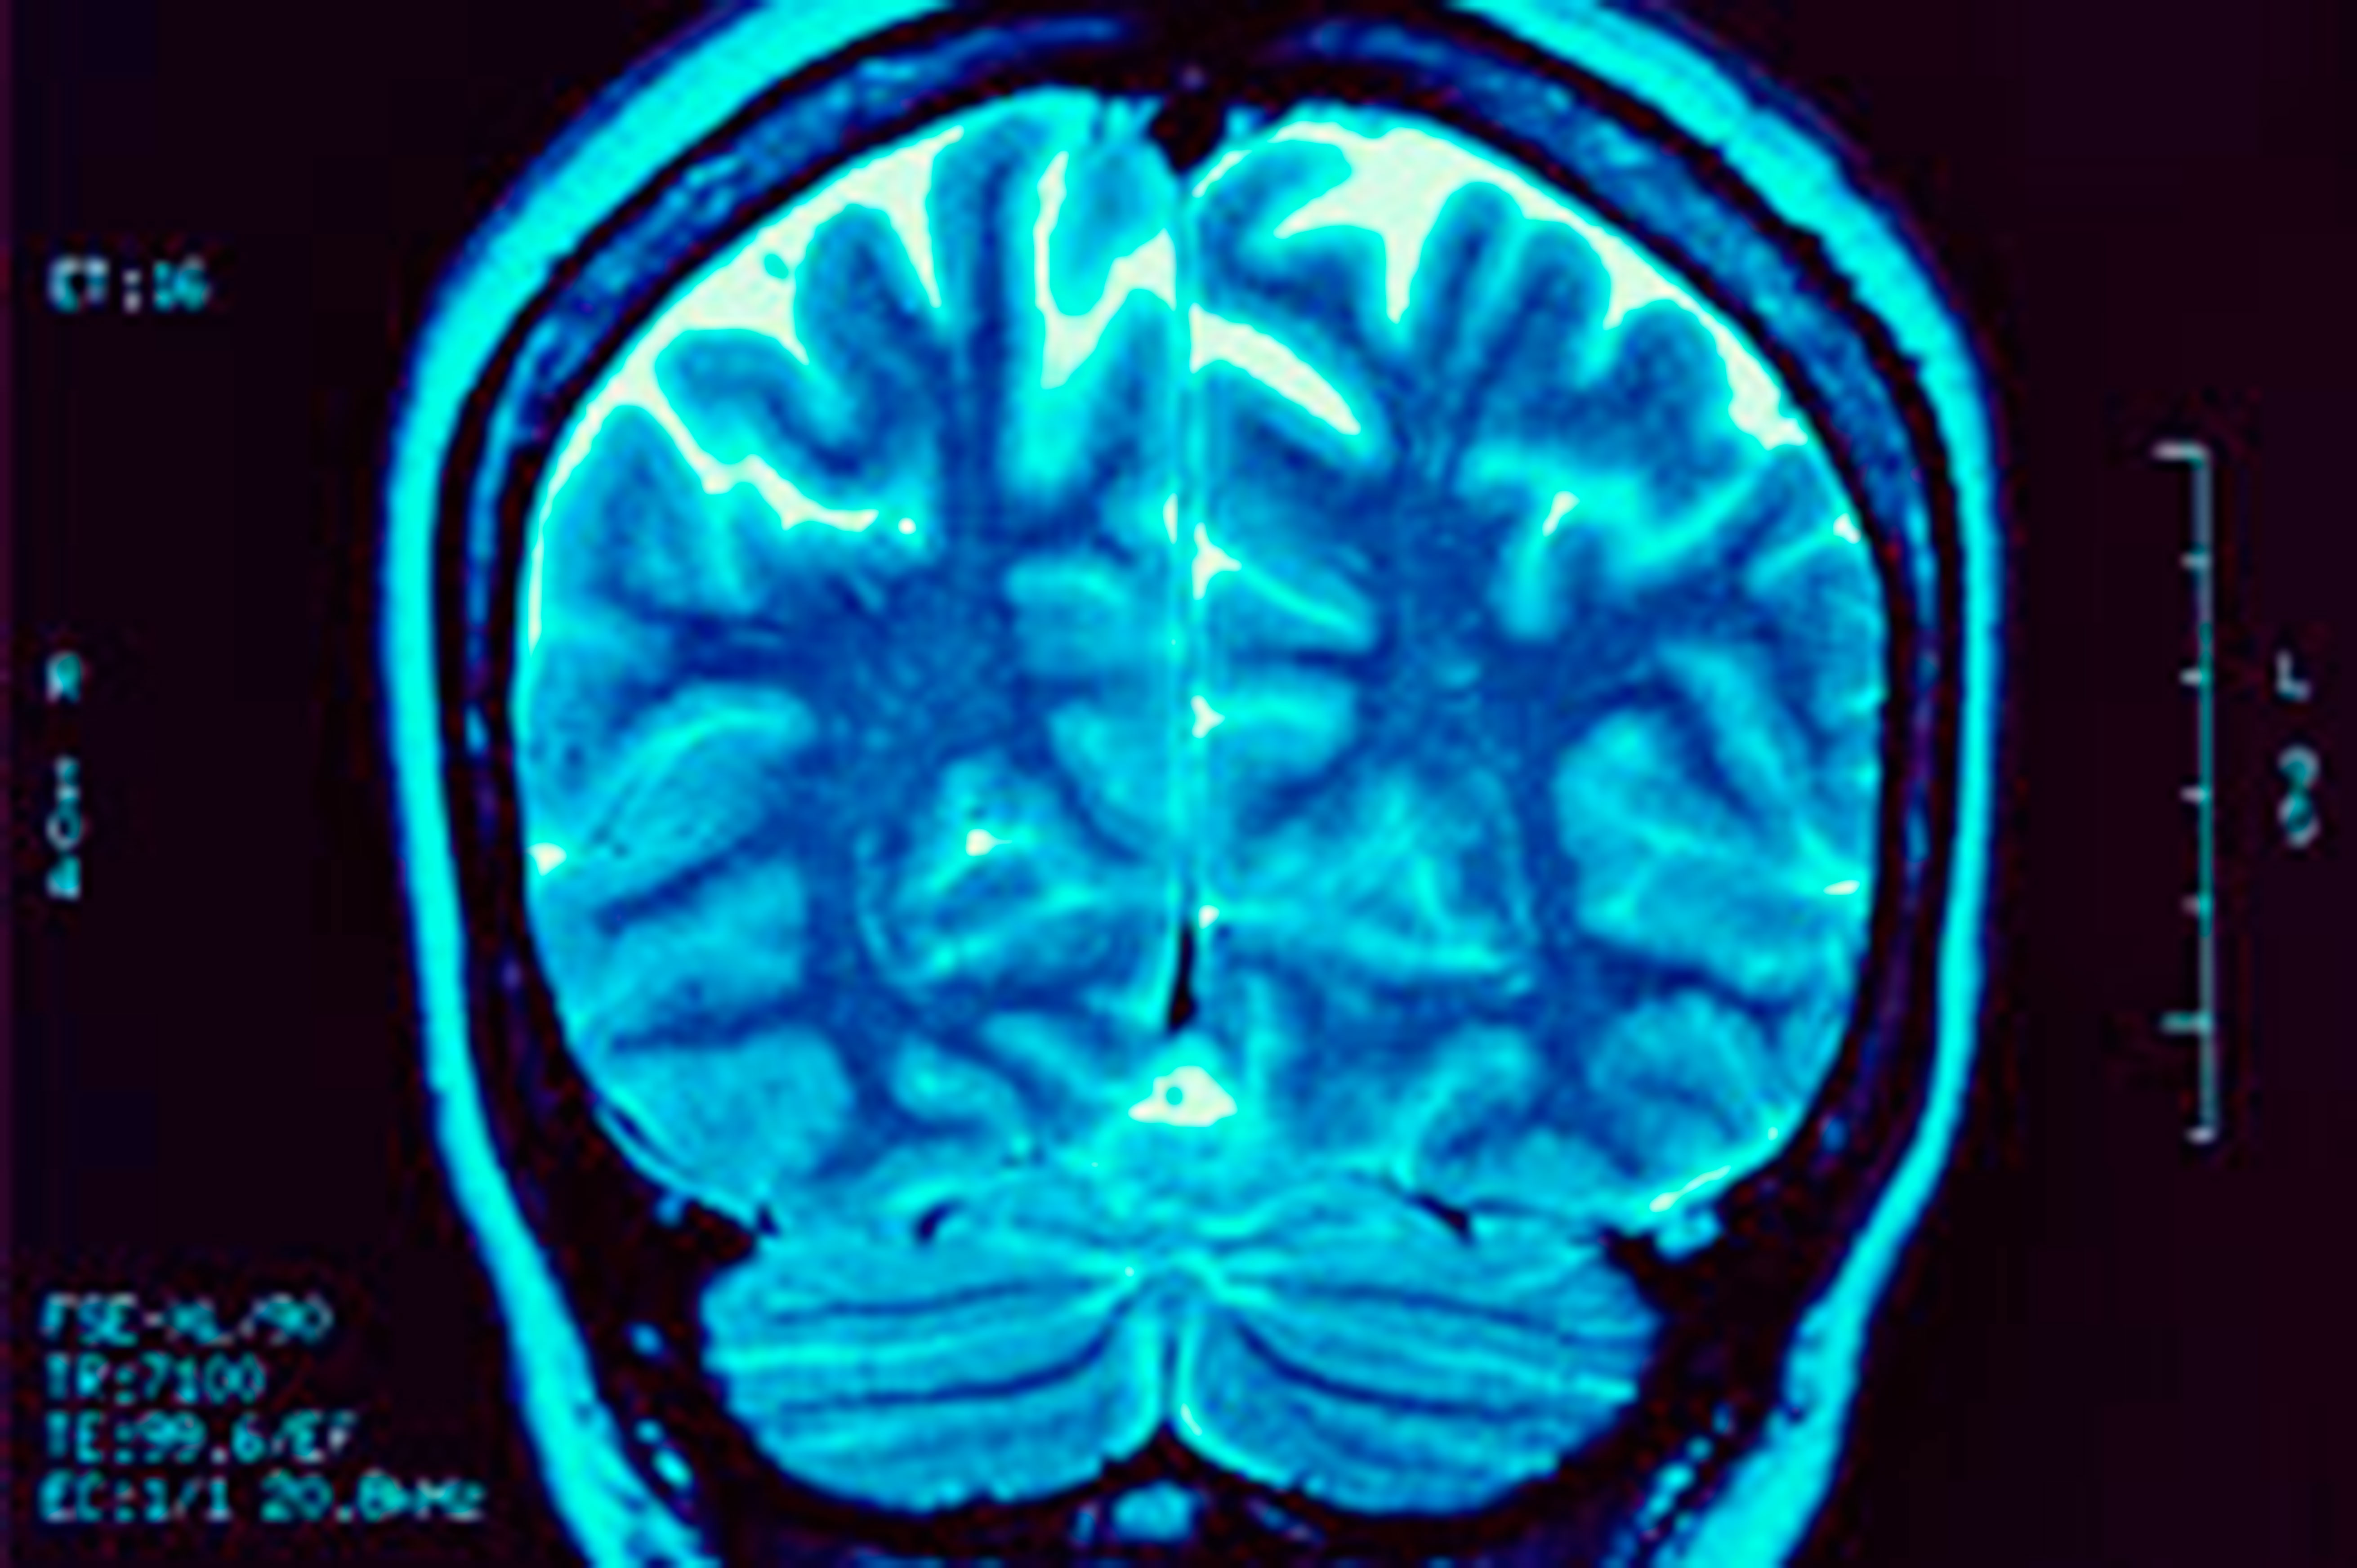

La Resonancia Magnética Nuclear (RMN) es una prueba diagnóstica con la que se obtienen imágenes del interior del cuerpo. Se basa en el procesamiento de radiofrecuencia que pasan por el paciente, el cual es sometido a un potente campo magnético. A diferencia del TAC o de las radiografías simples no usa radiaciones ionizantes (rayos X).

La Resonancia Magnética Nuclear permite obtener imágenes muy detalladas del cuerpo, en dos y en tres dimensiones, y desde cualquier perspectiva. Puede aportar información sobre patologías que no se vean con otras técnicas de imagen como la ecografía o el TAC. También se utiliza cuando están contraindicadas otras pruebas de imagen, como por ejemplo en caso de alergia al contraste iodado que se usa en el TAC.

• En la cabeza puede ver tumores, abscesos, aneurismas, sangrado, infartos o lesiones nerviosas. También puede servir para estudiar patologías en los ojos y en el oído o enfermedades degenerativas cerebrales.